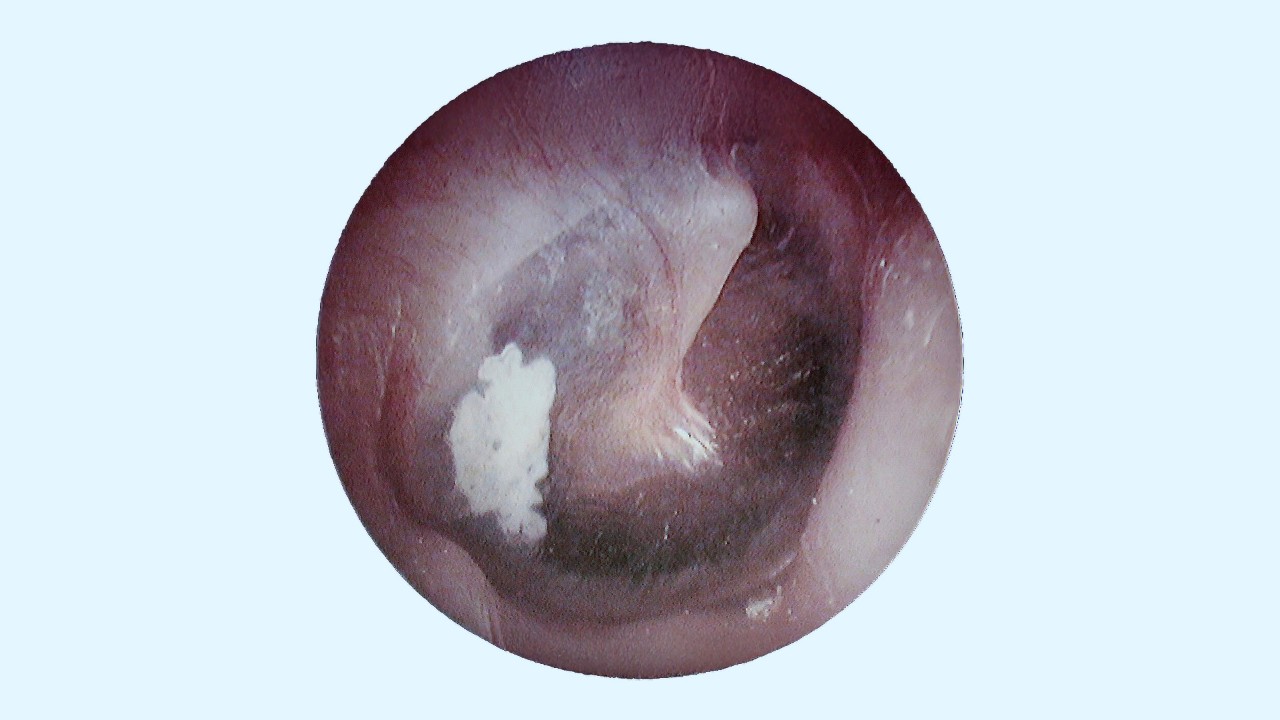

• Visible white or chalky plaques on the eardrum – Observed during an otoscopic examination, indicating the presence of tympanosclerosis.

• Otoscopy – A visual examination of the ear to identify white, hardened plaques on the tympanic membrane. This is the first step in detecting tympanosclerosis.